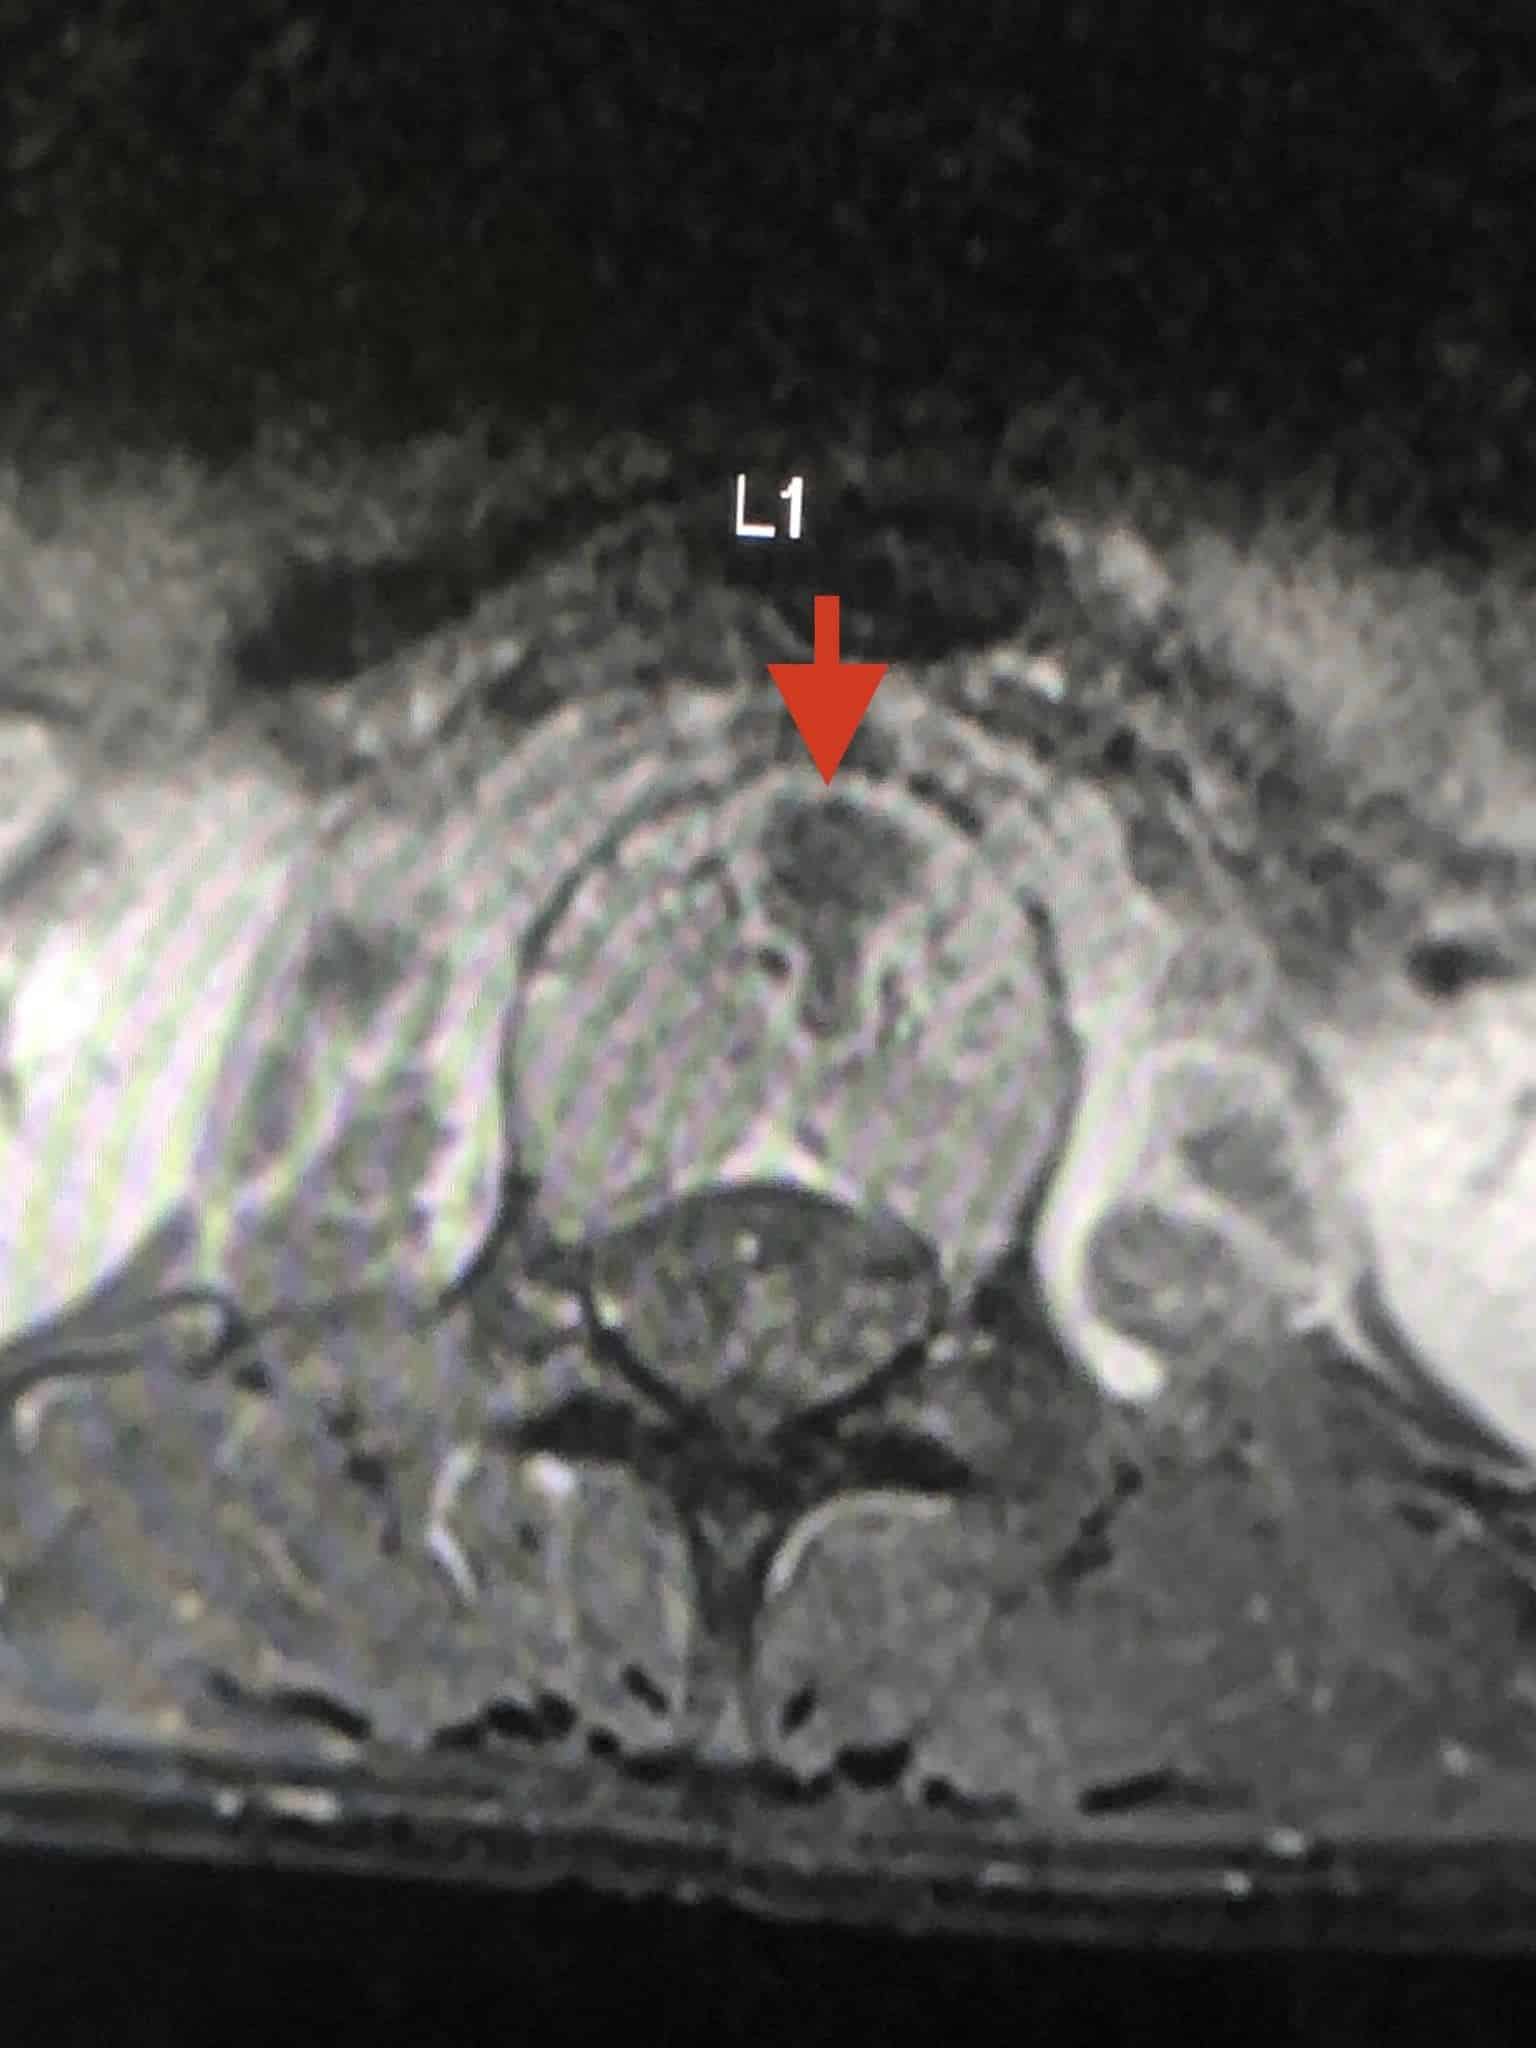

ตรวจร่างกายปกติ เจาะเลือดทุกอย่างปกติ เอกซเรย์ปอดและกระดูกสันหลังส่วนเอวปกติ ทำคลื่นแม่เหล็กไฟฟ้ากระดูกสันหลังส่วนเอว (MRI lumbar spine) ผิดปกติ สงสัยเป็นวัณโรคของกระดูกสันหลังส่วนเอว (lumbar spine) ชิ้นที่หนึ่ง และสงสัยมีการอักเสบรอบ ๆ เนื้อเยื่อกระดูกสันหลังส่วนเอวชิ้นที่ 1 และ 2 ร่วมด้วย (ดูรูป)